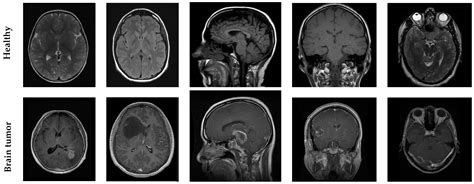

Image:

MRI for Brain Damage Detection

The intricate workings of the human brain are susceptible to diverse forms of damage, leading to cognitive deficits and functional impairments. Advanced Magnetic Resonance Imaging (MRI) technology plays a crucial role in detecting such damage and guiding patient management. While the clinical application of MRI for brain damage detection is well established, the mechanisms and subclinical changes identified by this modality often remain uncertain.